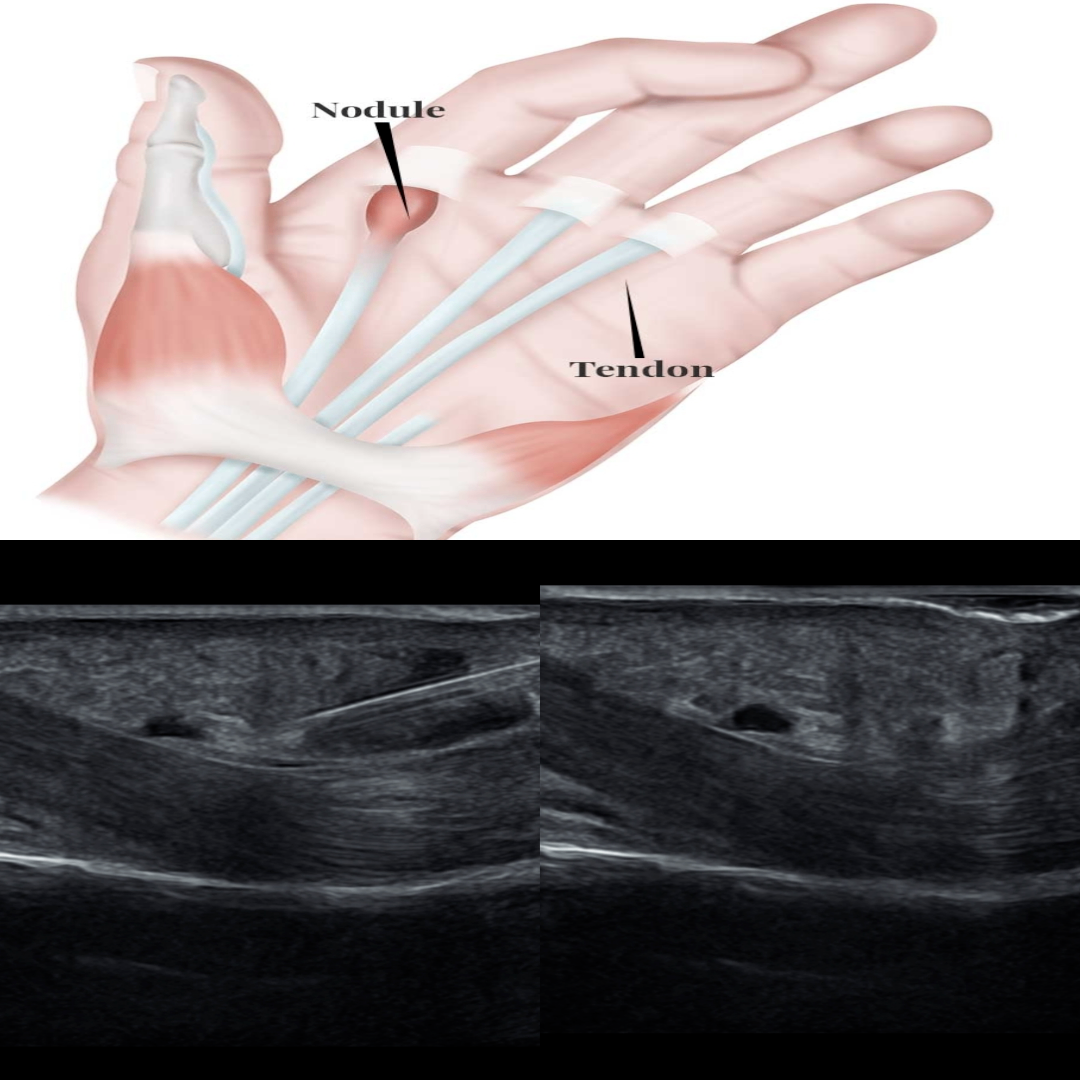

방아쇠 손가락

방아쇠 손가락은 손가락 굴곡근힘줄에 염증이 생겨서 아침에 굽혀진 손가락이 잘안펴지고 탁하면서 겨우 펴지면서 상당한 통증을 동반하는 질환입니다.

물리치료와 소염제에도  증상이 지속되면 주사치료를 할수 있는데 본원에서는 초음파 유도하 주사치료를 합니다. 초음파 유도하 주사를 하지않으면 정확히 약물을 투여할수 없으며 특히 하키스틱이라는 작고 섬세한 고해상도 탐촉자가 필요합니다.